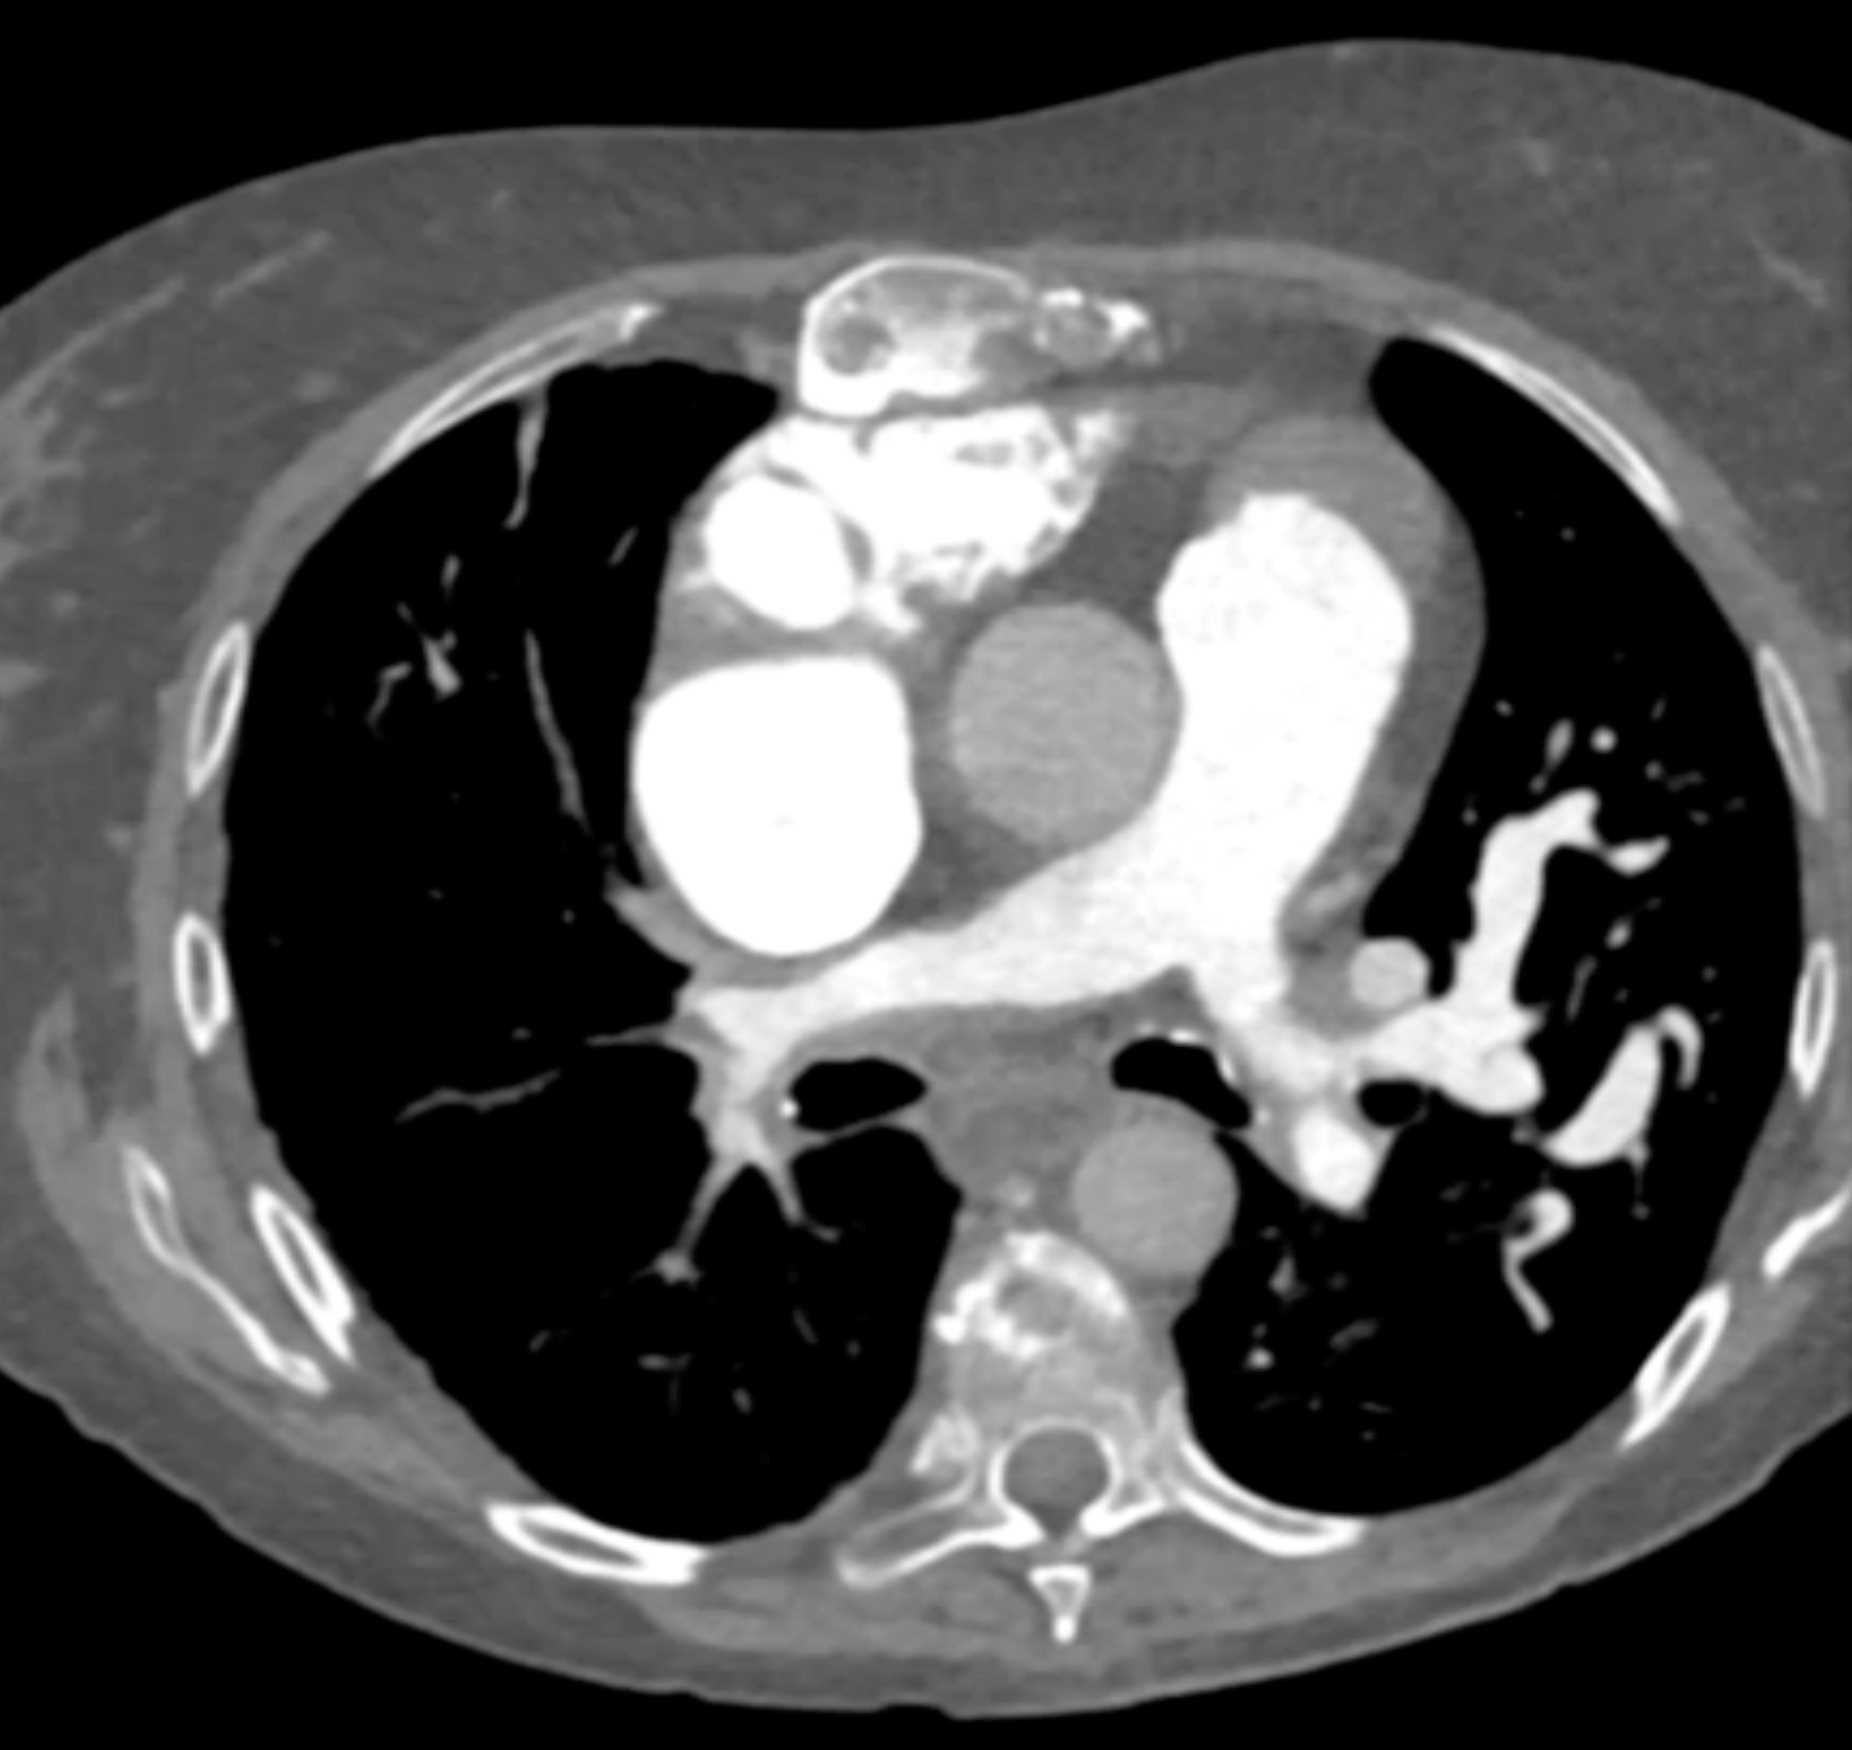

Fibrosing Mediastinitis involves the Pulmonary Artery and Vein